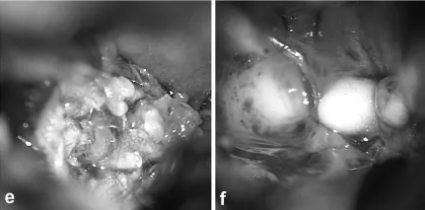

畸胎瘤中出现的牙齿、小骨骼、头发等实际上是由胚胎期生殖细胞异常分化引起的。通俗来说,就是原本应该分化成牙齿、骨骼、头发的细胞,在胚胎发育过程中出现异常,“跑”到了其他部位,但其实,这些只是成分类似的组织。

内镜下可见肿瘤内的头发和牙齿